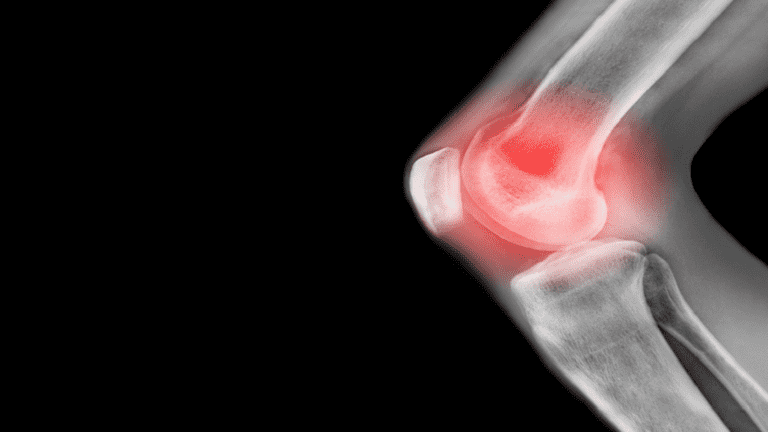

خبرني - يمكن أن يؤثر ألم الركبة المزمن على نشاطك، ويقول الخبراء إن التمارين الأساسية يمكن أن تساعد بشكل كبير في معظم مشاكل الركبة.

وفي معظم الحالات، يتمثل سبب آلام الركبة في الصدمة الناجمة عن إصابة رياضية أو إصابة في العمل.

ويعد تلف الغضروف داخل الركبة وتمزق الأربطة، من الإصابات الشائعة التي تحدث بسبب الصدمة.

وفي حين أن تمزق الغضروف يمكن أن يشفى من تلقاء نفسه، إلا أن الخبراء يحذرون من أن تلف الأربطة قد يتطلب إجراء عملية جراحية.